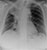

Large pleural effusion

- Here the trachea and mediastinum are deviated to the right.

- There is opacification of the left lower hemithorax due to a pleural effusion (fluid gathering in the pleural space). This has PUSHED the whole mediastinum to the right.

- In this case the patient was found to have mesothelioma, a malignancy of the pleura related to asbestos exposure.